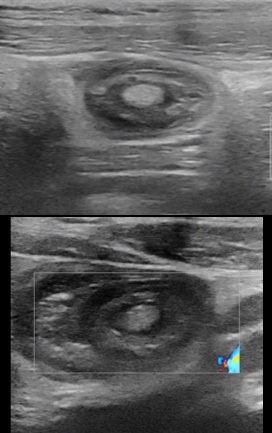

A 15-year-old male patient, with a history of intermittent abdominal pain, two episodes of bleeding considered to anal fissure, and of chronic constipation consulted twice in the emergency department for ileo-ileal intussusception more than a year apart. At the first presentation, the patient consult with the general condition preserved, apyrexia, bilious vomiting. The physical examination found pain in the right hypochondrium and sub umbilical, a soft abdomen, no tusks or palpable abdominal mass. The ultrasound performed found ileo-ileum intussusception without any sign of complication with the intussusception tube in the pelvic position (Figure1).

Figure 1: Ultrasound at first presentation, visualized hyperechoic intraluminal image, well limited, next to the distal part of the intussusception tube, 4 mm thick, 11 mm long.

An hour later in the emergency room there is no more pain, a new ultrasound is requested which does not found the intussusception. He discharges and an appointment was set for him in three months in the event of no recurrence. The patient was seen again on the scheduled date and there was no recurrence or sign of complication. Seventeen months later from the first episode of invagination, the patient consults to the emergency room for episodes of severe abdominal pain localized in the epigastric region, of high intensity, without signs of irradiation and similar to those of the previous attack, no transit since two days (usual, consistent with his chronic constipation). The general condition of the patient is preserved, temperature at 36.4°C, pulse: 90 per minute, SaO2 : 100%, weight: 57.7 kg, digital pain assessment: 8, spontaneous ventilation ambient air: 18 cycles per minute, pale coloring, nauseous, but no vomiting. Physical examination revealed epigastric pain, a numb, helpless, unbloated abdomen, no palpable organomegaly. Ultrasound performed in an emergency found ileum intussusception at the epigastric location with the presence of a probable fatty structure mimiking to a mesenteric fat or a lipoma, a few visible common mesenteric lymph nodes, no coeliomesenteric or retroperitoneal adenopathy, there is no intra-abdominal fluid effusion (Figure 2).